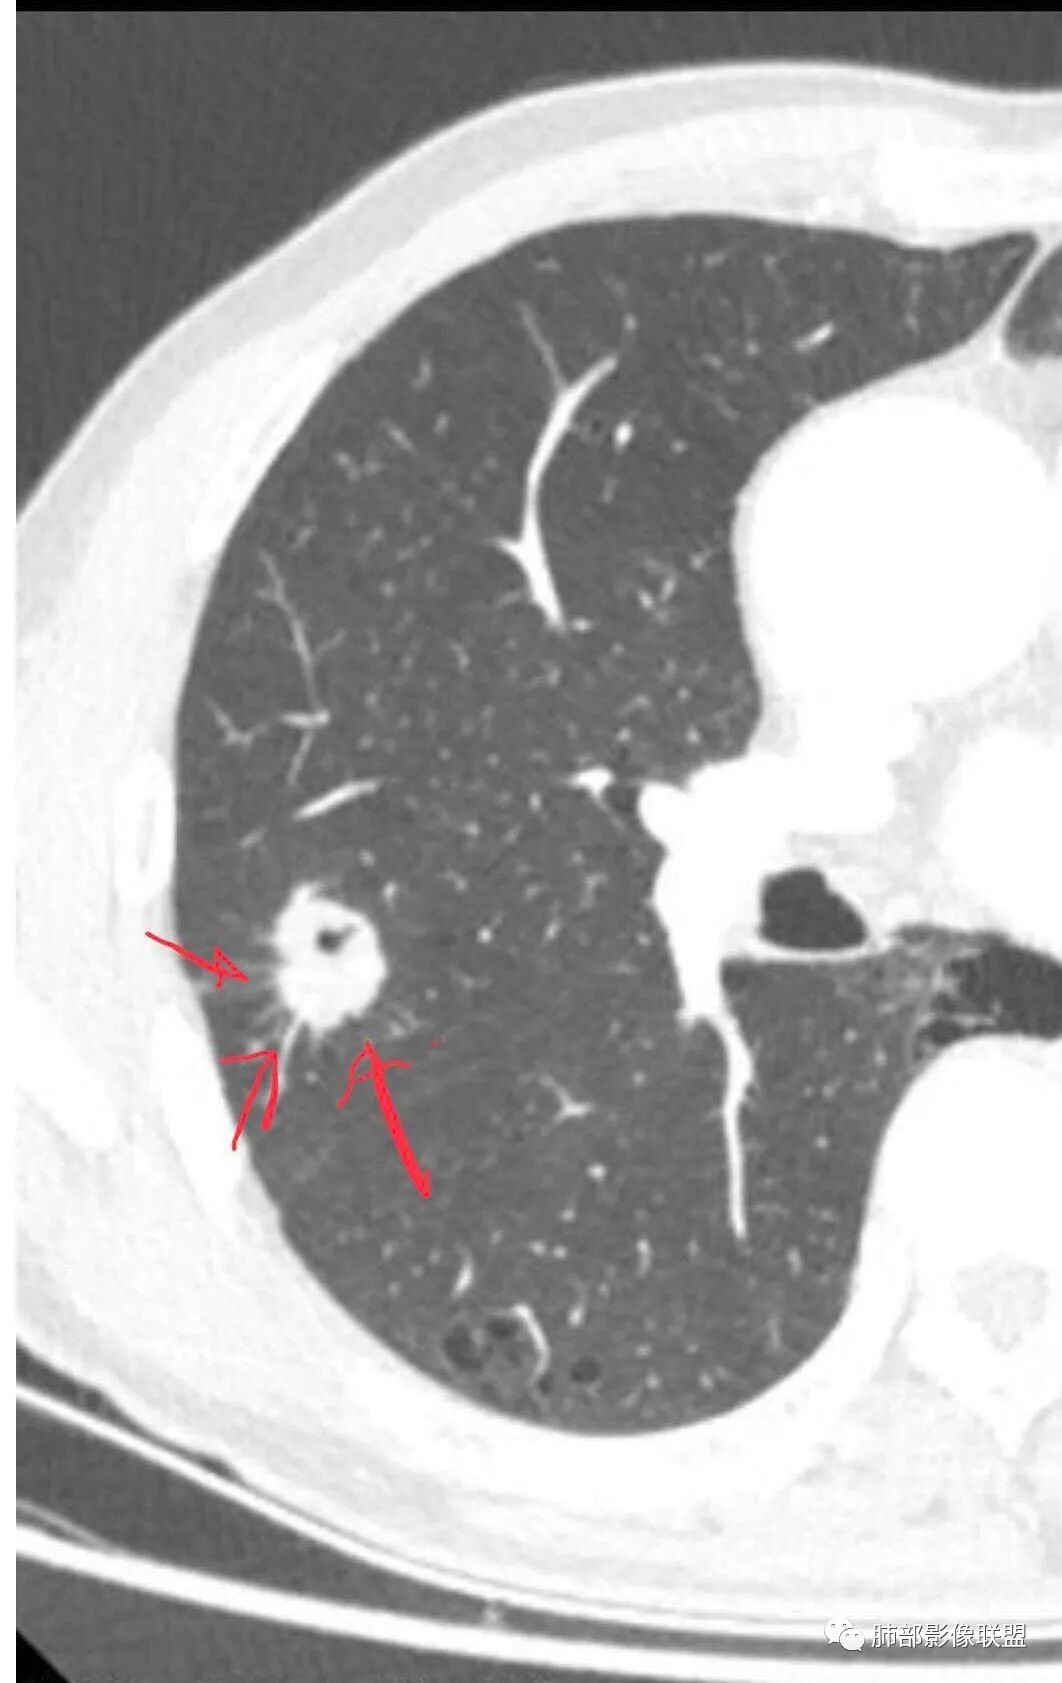

右肺上叶结节,周围毛刺明显,其内有小炮征,分叶,强化中度,其内可见坏死,支气管有截断,考虑腺癌,鳞癌待排。病灶的上缘有一个小支气管进入,然后截断了

我觉得搞清楚空洞还是空泡也很重要,空泡指向癌,空洞癌、结核、PC都可以

就这一例而言我也不知道是空泡还是空洞,感觉不具有形成空洞的病理基础(坏死物经支气管排出);所以一开始就请教老师了

毛勤香:

不像空泡,有点鬼脸的感觉,增强坏死多,但毛刺也多

空泡是绕正常的肺组织或支气管生长形成,空洞是实性组织坏死,坏死物排出所致。但这么小不好区别。

@毛勤香 柳州龙潭医院影像 毛老师,是因为其内空腔不规则,考虑空洞吗?

再加上增强其内有坏死,考虑这个是空洞吗?

晨读:男,67岁,体检发现右肺结节。近圆形,支气管及伴行血管进入结节,进入结节后支气管堵塞,血管走形尚自然,结节内血管边缘凹凸不平。远端边缘见毛刺(软毛刺?)及分叶。见胸膜牵拉。实变中见空洞。整体膨胀感不明显。考虑炎性肉芽肿可能,隐球菌病可能性大。注意鉴别鳞癌、结核。

这个病例确实有很多隐球菌的特点,包括周围的卫星灶、周围的毛刺,它没有粗短的毛刺,它是稍长一点、柔弱一点的。我是觉得这个符合脐凹征,所以我觉得恶性不能排除,结果错了,是炎性。

这个大部分边缘稍微偏平直一点,血管走行非常自然,包括里面的空泡征样的,影子很干净,边界很光滑,都是些炎性特点。